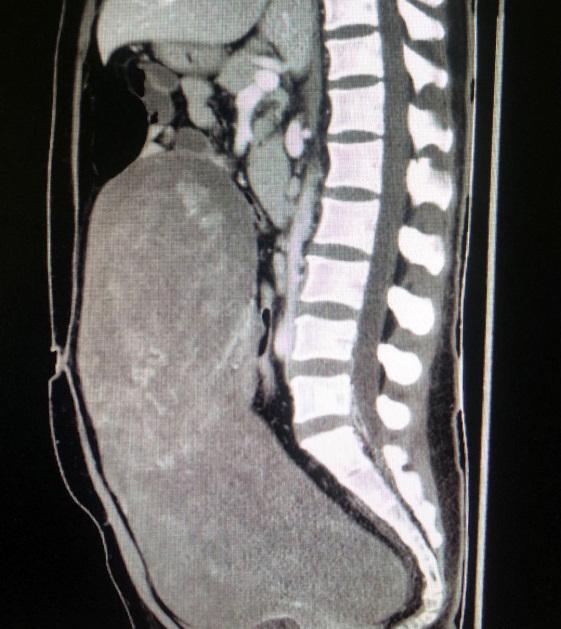

去年11月开始,42岁的张女士突感腹部胀痛难忍,肚子日渐肿胀,腹围增大。2周后,于当地医院就诊,经检查显示,张女士的腹腔内有一巨大肿物,医生建议张女士尽快转诊上级医院进行手术治疗,否则将有生命危险。了解到北京友谊医院肿瘤救治的综合实力后,张女士在家人的陪同下慕名前来就诊。经诊断,张女士盆腹腔瘤体巨大,上界达膈下,向下充满盆腹腔,侵袭范围如此之大的盆腔肿物非常罕见。为了能准确评估肿瘤来源,血供、侵及范围,以便后续手术治疗,需要对张女士进行增强影像学检查。但因患者本身患有输尿管、肾结石,加上肿瘤压迫,导致肾功能不全,处于肾衰竭边缘,如若进行增强影像学检查会有急性肾衰竭的危险。

12月10日,泌尿科医师宁晨为张女士成功放置双侧输尿管支架,引流出脓性尿液。经抗感染治疗,张女士血肌酐轻微下降。在影像科大力协助下进行了增强CT检查及三维血管重建。

12月18日上午,经过了充分的术前准备,手术正式开始。麻醉科主任医师柯敬东担任主麻医师,手术由妇产科郝增平主任主持,主任医师金影、主治医师金华共同操刀手术。手术团队在开腹探查后发现患者盆腹腔巨大肿瘤长径40cm,来自左侧子宫阔韧带,压迫周围组织呈膨胀性生长,达上腹腔,瘤体表面血运丰富,并与肠管及周围组织粘连。郝增平主任有着妇科大型疑难手术丰富的经验,在金影主任医师的默契配合下,一步一步谨慎的分离粘连并牢靠止血,经细致谨慎的操作,该手术历时2个小时终于顺利完成,术中出血仅100ml。该瘤体体积40cm×31cm×20cm,重达13斤,术后诊断为子宫阔韧带粘液样及脂肪平滑肌瘤。张女士术后恢复良好,7天后康复出院。手术后肾功能逐渐恢复正常,于当地医院定期随访。